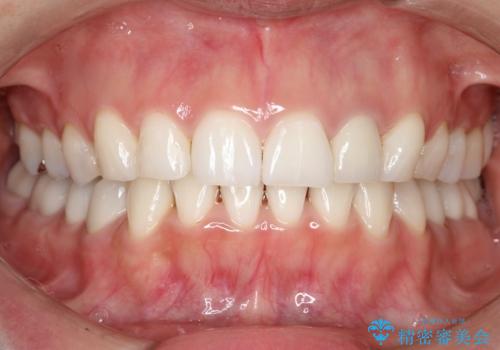

- 前歯の凸凹と顎の偏位を主訴に来院されました。

下顎の偏位を認めましたが、外科矯正を希望されなかったためできる範囲で顎の偏位を治すことができるよう治療を行なっております。

治療開始前に、下顎位の評価をおこなうことで、完成度の高い治療を行うことができました。